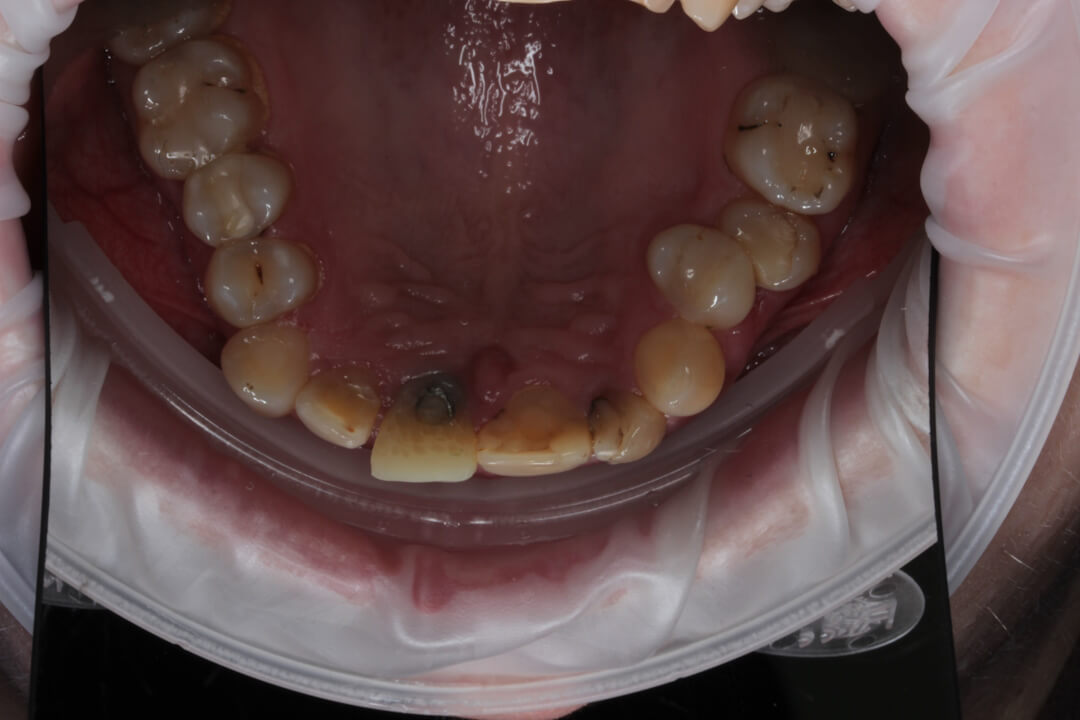

Рис. 4. Вид временной коронки на винтовой фиксации с окклюзионной поверхности. Шахта титанового абатмента закрыта фотополимеризационным материалом.